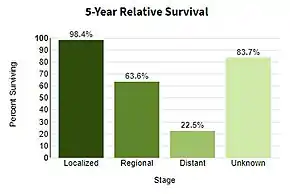

| Prognosis | Five-year survival rates in US 99% (localized), 25% (disseminated)[4] |

Using sunscreen and avoiding UV light may prevent melanoma.[2] Treatment is typically removal of the melanoma and potentially affected tissue (border around the melanoma) by surgery.[1] In those with slightly larger cancers, nearby lymph nodes may be tested for spread (metastasis).[1] Most people are cured if spread has not occurred.[1] For those in whom melanoma has spread, immunotherapy, biologic therapy, radiation therapy, or chemotherapy may improve survival.[1][12] With treatment, the five-year survival rates in the United States are 99% among those with localized disease, 65% when the disease has spread to lymph nodes, and 25% among those with distant spread.[4] The likelihood that melanoma will reoccur or spread depends on its thickness, how fast the cells are dividing, and whether or not the overlying skin has broken down.[2]

Stage IV melanoma, in which it has metastasized, is the most deadly skin malignancy: five-year survival is 22.5%.[131] When there is distant metastasis, the cancer is generally considered incurable. The five-year survival rate is less than 10%.[146] The median survival is 6–12 months. Treatment is palliative, focusing on life extension and quality of life. In some cases, patients may live many months or even years with metastatic melanoma (depending on the aggressiveness of the treatment). Metastases to skin and lungs have a better prognosis. Metastases to brain, bone and liver are associated with a worse prognosis. Survival is better with metastasis in which the location of the primary tumor is unknown.[147]